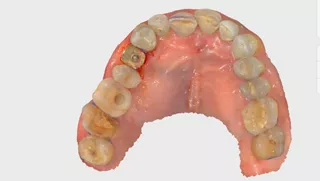

A 78-year-old male in good general health, with no medication and a negative smoking history, presented with mobility of the maxillary right second premolar (tooth 15) (Fig 1a. 1b). Clinical examination revealed severe occlusal wear, plaque accumulation, subgingival calculus, bleeding on probing, and multiple carious lesions. Periodontal assessment showed probing depths >10 mm and grade III mobility. CBCT confirmed circumferential vertical bone loss around tooth 15 and generalized periodontal involvement, indicating a hopeless prognosis and the need for extraction (Fig 1c).

1a. 1b. 1c. CBCT and panoramic views showing severe bone loss around tooth 15, confirming hopeless prognosis.